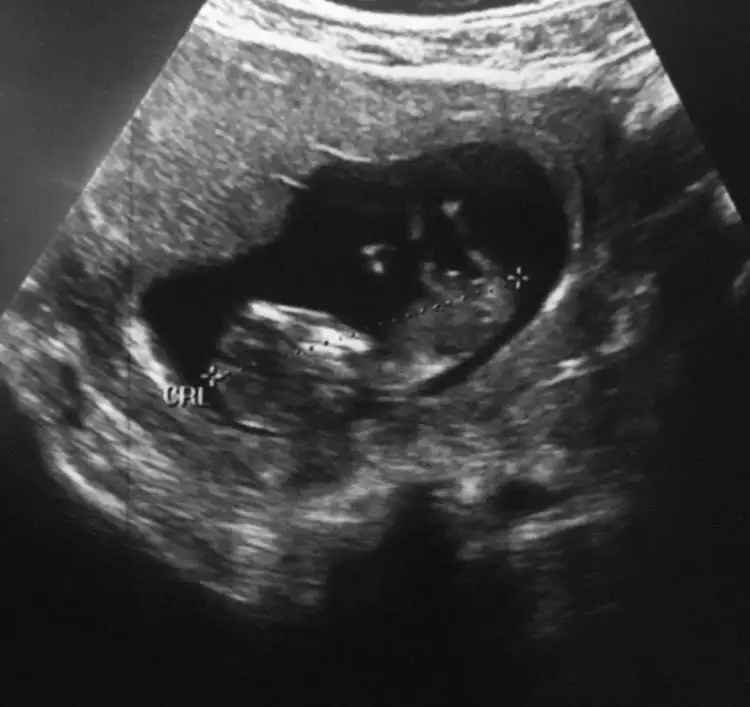

KizEki Görüntüle 2593205 Eki Görüntüle 2593206 Eki Görüntüle 2593208 Eki Görüntüle 2593209 M mely15Ikra meyra bakabilirmisinix bi arkadasın çok merak ediyo

Banada bakarmısınız 12+2 günlükErkek ve kız için 11 yada 12 hafta usg görüntüsü olmalı açıklamalar asagıda yazıyorrabbim herkesin gönlüne göre nasip etsin inşallah .. ecmain

Erkek gibi 12+ da paylaşın emin olamadımKızlar 11+5 sizce ne cinsiyeti ben çıkıntıyı anlayamadım lütfen söyleyin çatlıcam meraktan

Net değil başka usg paylaşımBanada bakarmısınız 12+2 günlük